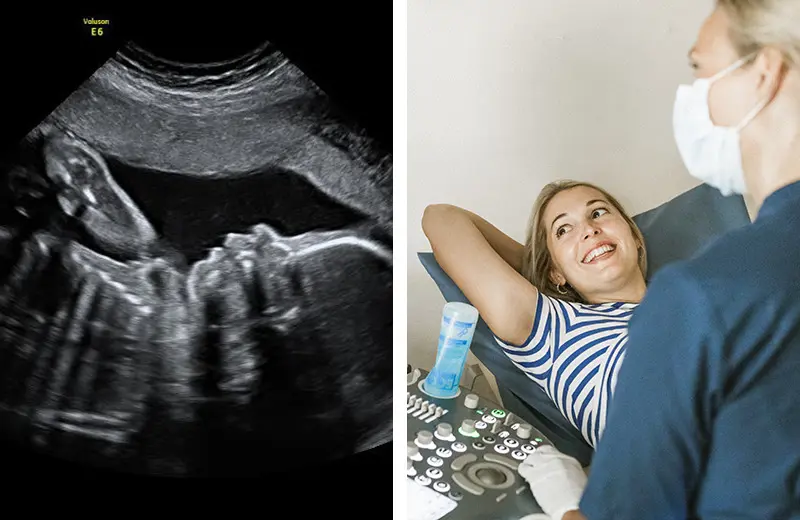

Jag jobbar som barnmorska på Capio Ultraljudsbarnmorskorna i Stockholm. Jag har varit här i snart 4 år och arbetat som barnmorska i 8 år. Vi arbetar med fosterdiagnostik och undersöker med hjälp av ultraljud gravida kvinnor. Vår uppgift är att bekräfta det normala samt att upptäcka avvikelser.

Här på Ultraljudsbarnmorskorna är vi är totalt 12 barnmorskor som är specialiserade på ultraljud, och vi undersöker ungefär 16 500 kvinnor per år. Här erbjuder vi bland annat tidigt ultraljud, KUB-test och rutinultraljud men vi tar även emot överburna kvinnor för kontroll.

Vi är den näst största ultraljudsmottagningen i Stockholm. Här i Liljeholmen ligger vår stora mottagning men vi har även en mottagning i Täby.